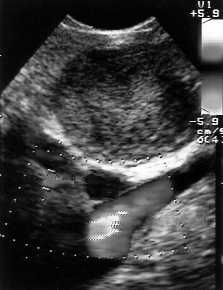

Эндосонография (ЭндоУЗИ, эндоскопическая ультрасонография)

Эндосонография — диагностическая методика , высокотехнологическое исследование, одновременно сочетающее в себе возможности эндоскопической и ультразвуковой диагностики.

Для исследования используют гибкий эндоскоп с видеокамерой и ультразвуковым датчиком. Его можно ввести в пищевод, желудок, двенадцатиперстную, прямую, толстую кишку, а также в дыхательные пути. Во время обычного ультразвукового исследования через кожу, когда нужно осмотреть орган, который находится глубоко, страдает четкость изображения. Эндосонография решает эту проблему. При помощи эндоскопа УЗ-датчик подводят максимально близко к исследуемому образованию. Во время исследования врач может провести тонкоигольную биопсию подозрительного образования. Использование в приборе очень высоких частот ультразвука (5,0; 7,5; 12 и 20 МГц) обеспечивает высокое качество изображения с разрешающей способностью менее 1 мм, недоступное другим методам исследования, таким как обычное ультразвуковое исследование, компьютерная и магнитно-резонансная томография, эндоскопическая холангиопанкреатикография. При этом эндосонография не сопряжена с риском рентгенологического облучения персонала и пациента, отсутствует опасность возникновения осложнений, свойственных ЭРХПГ.

Как проводится эндосонография?

Эндосонография верхних отделов желудочно-кишечного тракта напоминает гастроскопию, нижних отделов - сигмоскопию, колоноскопию. Процедура продолжается от 20 до 60 минут. Она занимает больше времени, когда ее дополняют тонкоигольной биопсией. Обычно эндосонографию проводят в состоянии медикаментозного сна - разновидность легкого наркоза. В этом состоянии пациент во время процедуры практически ничего не чувствует, может ощущать лишь небольшой дискомфорт. В ходе эндосонографии врач следит за артериальным давлением пациента, пульсом, уровнем кислорода в крови. Примерно через час врач разрешает встать, и, если состояние пациента в порядке, отпускает домой. В этот день нельзя садиться за руль и заниматься работой, требующей концентрации внимания.